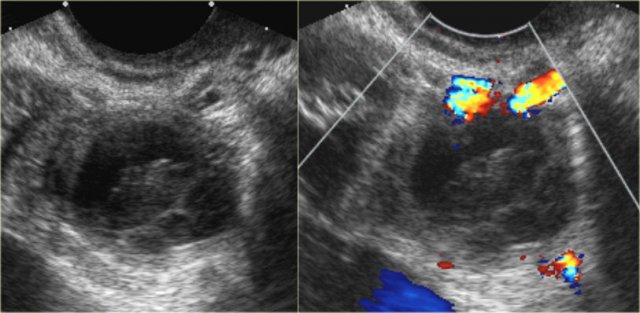

Các hình ảnh siêu âm cho thấy nhiều tổn thương buồng trứng phải đơn giản và một tổn thương phức tạp (mũi tên đỏ).

Tổn thương sau biểu hiện hồi âm mức thấp lan tỏa và không có tín hiệu dòng chảy trên Doppler.

Lưu ý có xuyên âm tốt (mũi tên xanh).

Các đặc điểm này gợi ý sự hiện diện của nang xuất huyết.

Tiếp tục xem các hình ảnh MRI.